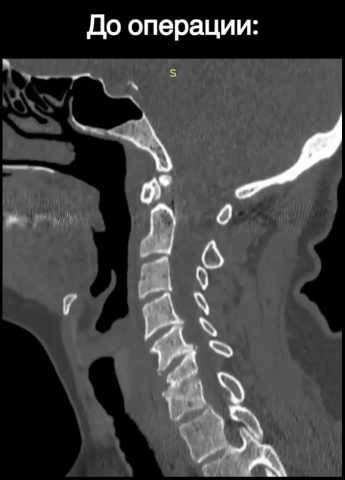

– Пациентку стали беспокоить чувство онемения и неприятные ощущения в руках. При дообследовании врачи выявили патологический перелом тел шестого и седьмого позвонков шейного отдела вследствие спондилодисцита (воспалительное заболевание позвоночника), – поделились медики. – Тогда было принято решение провести операцию.

Хирургам было необходимо устранить компрессию спинного мозга, а также удалить тела поражённых позвонков и зафиксировать позвоночник. Когда это было сделано, врачи приступили к установке телоскопического телозамещающего импланта.